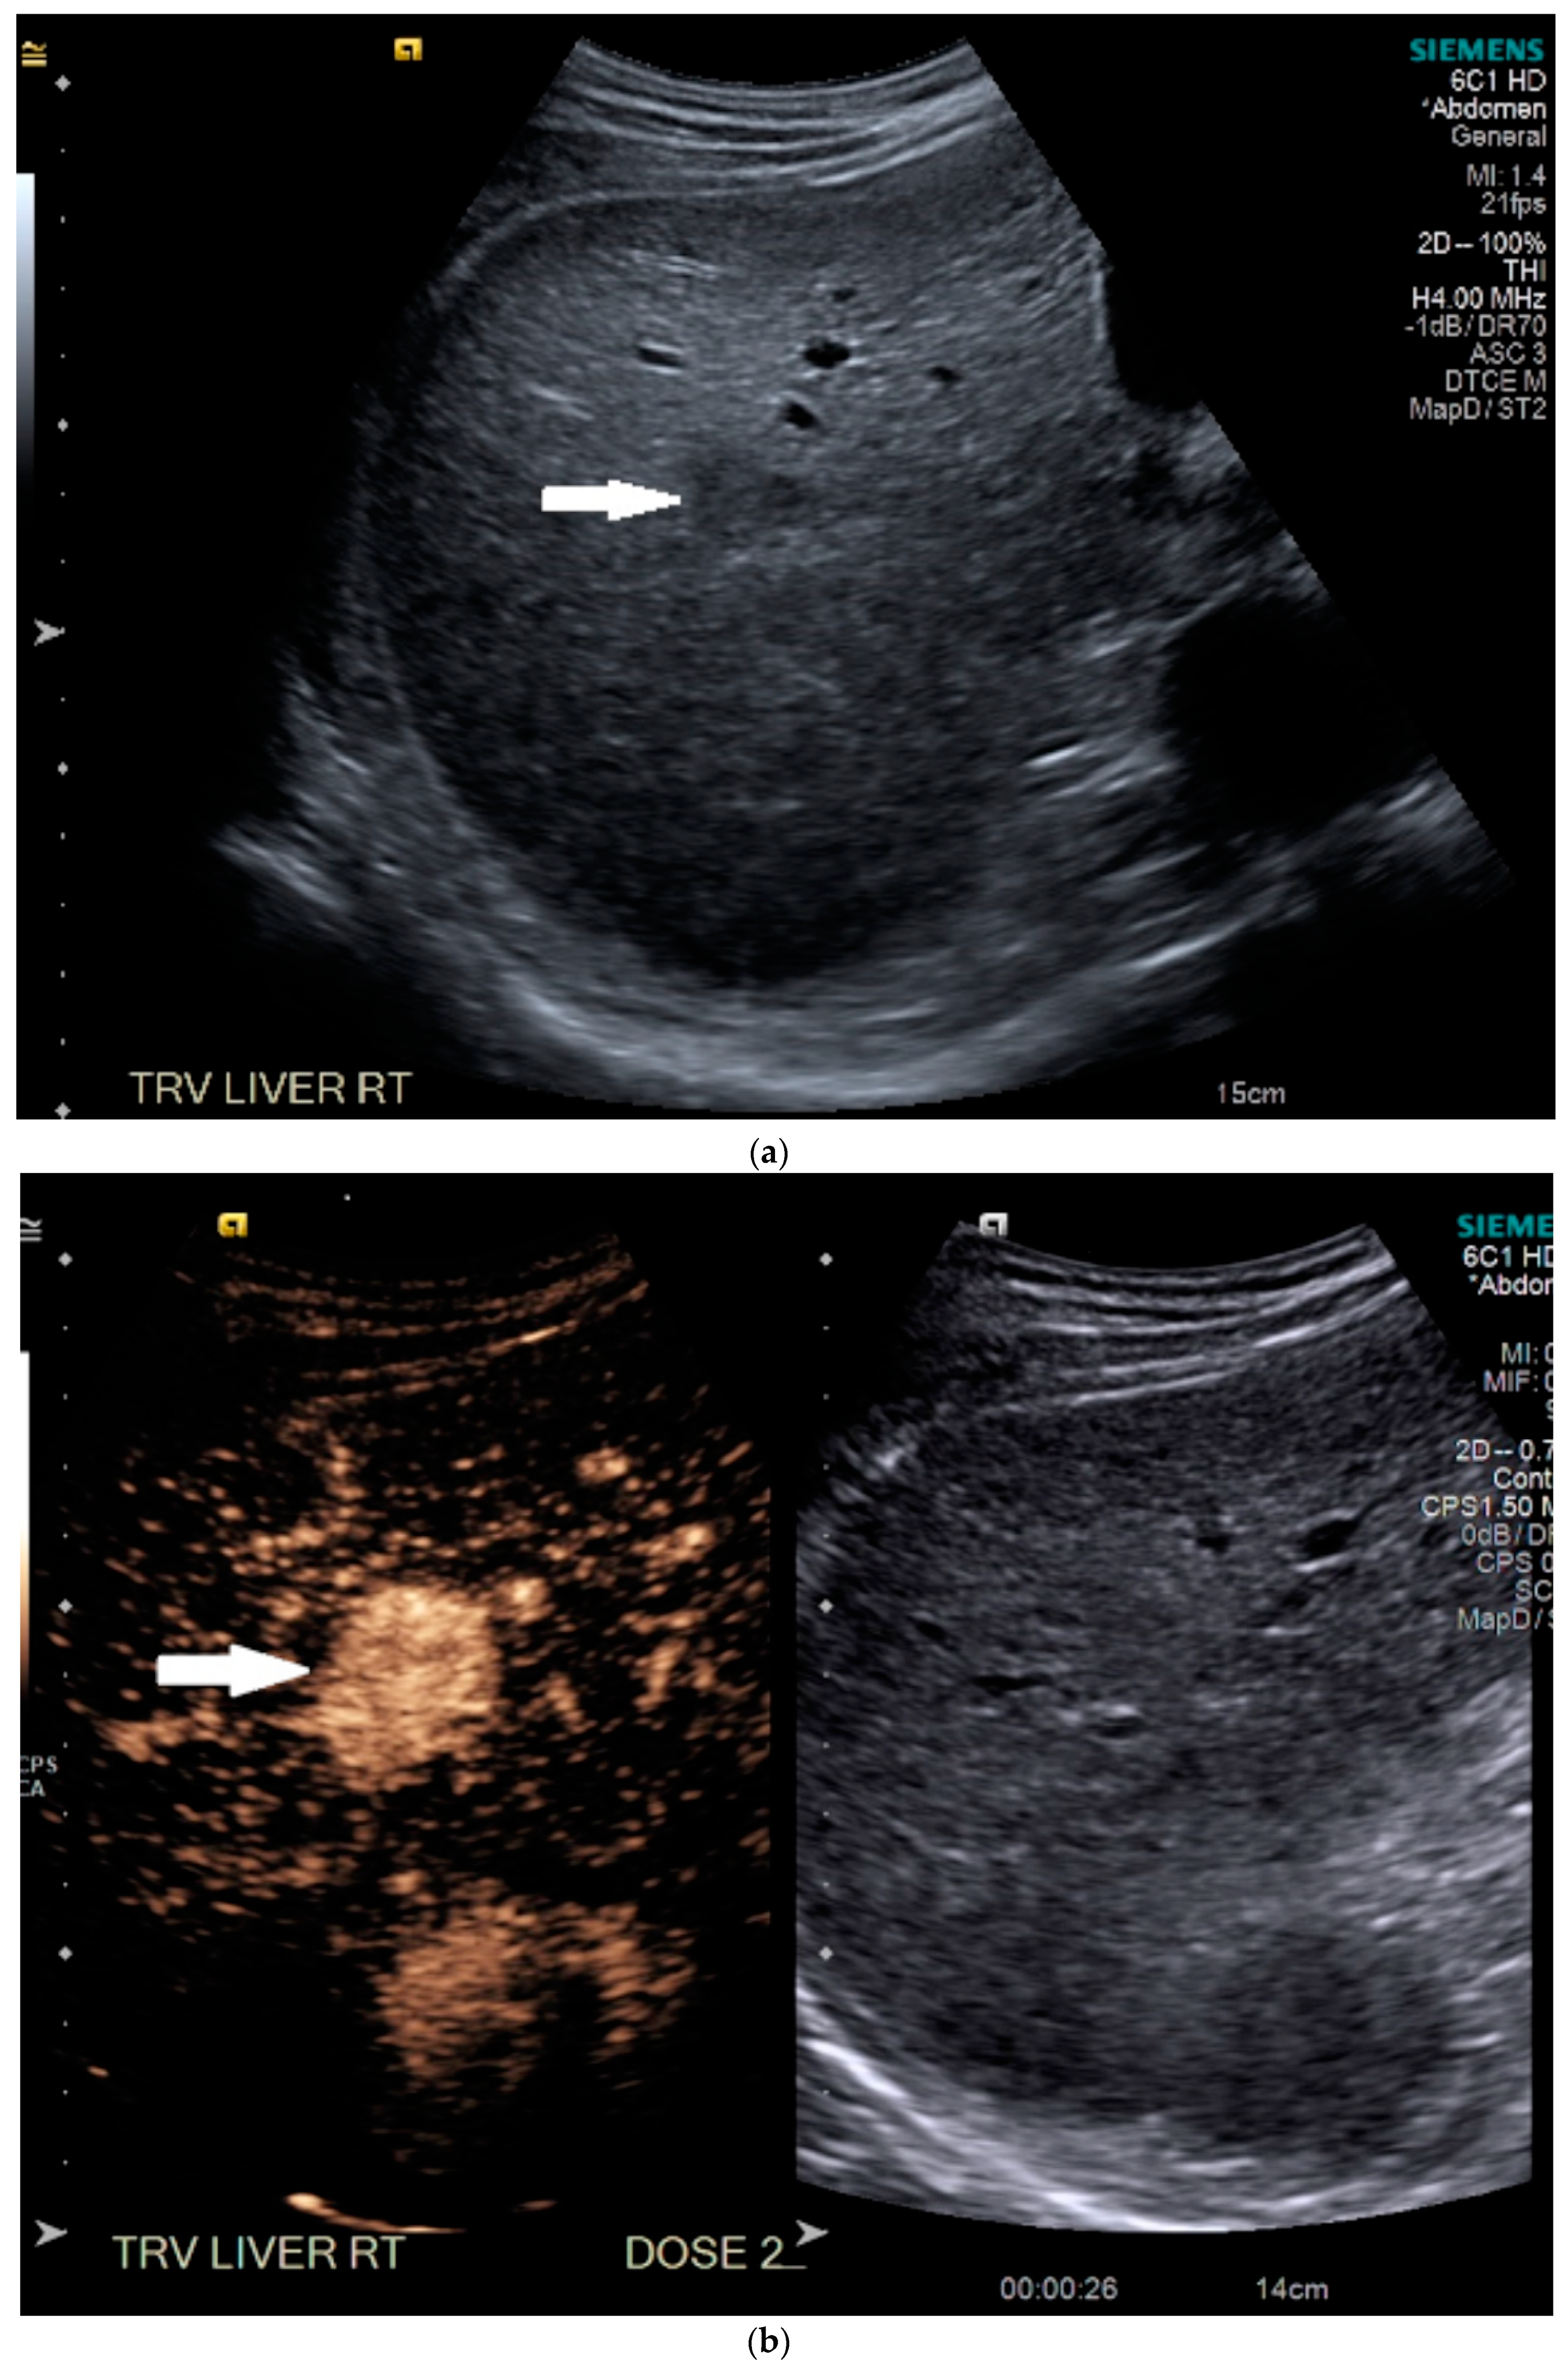

3.1. Case 1